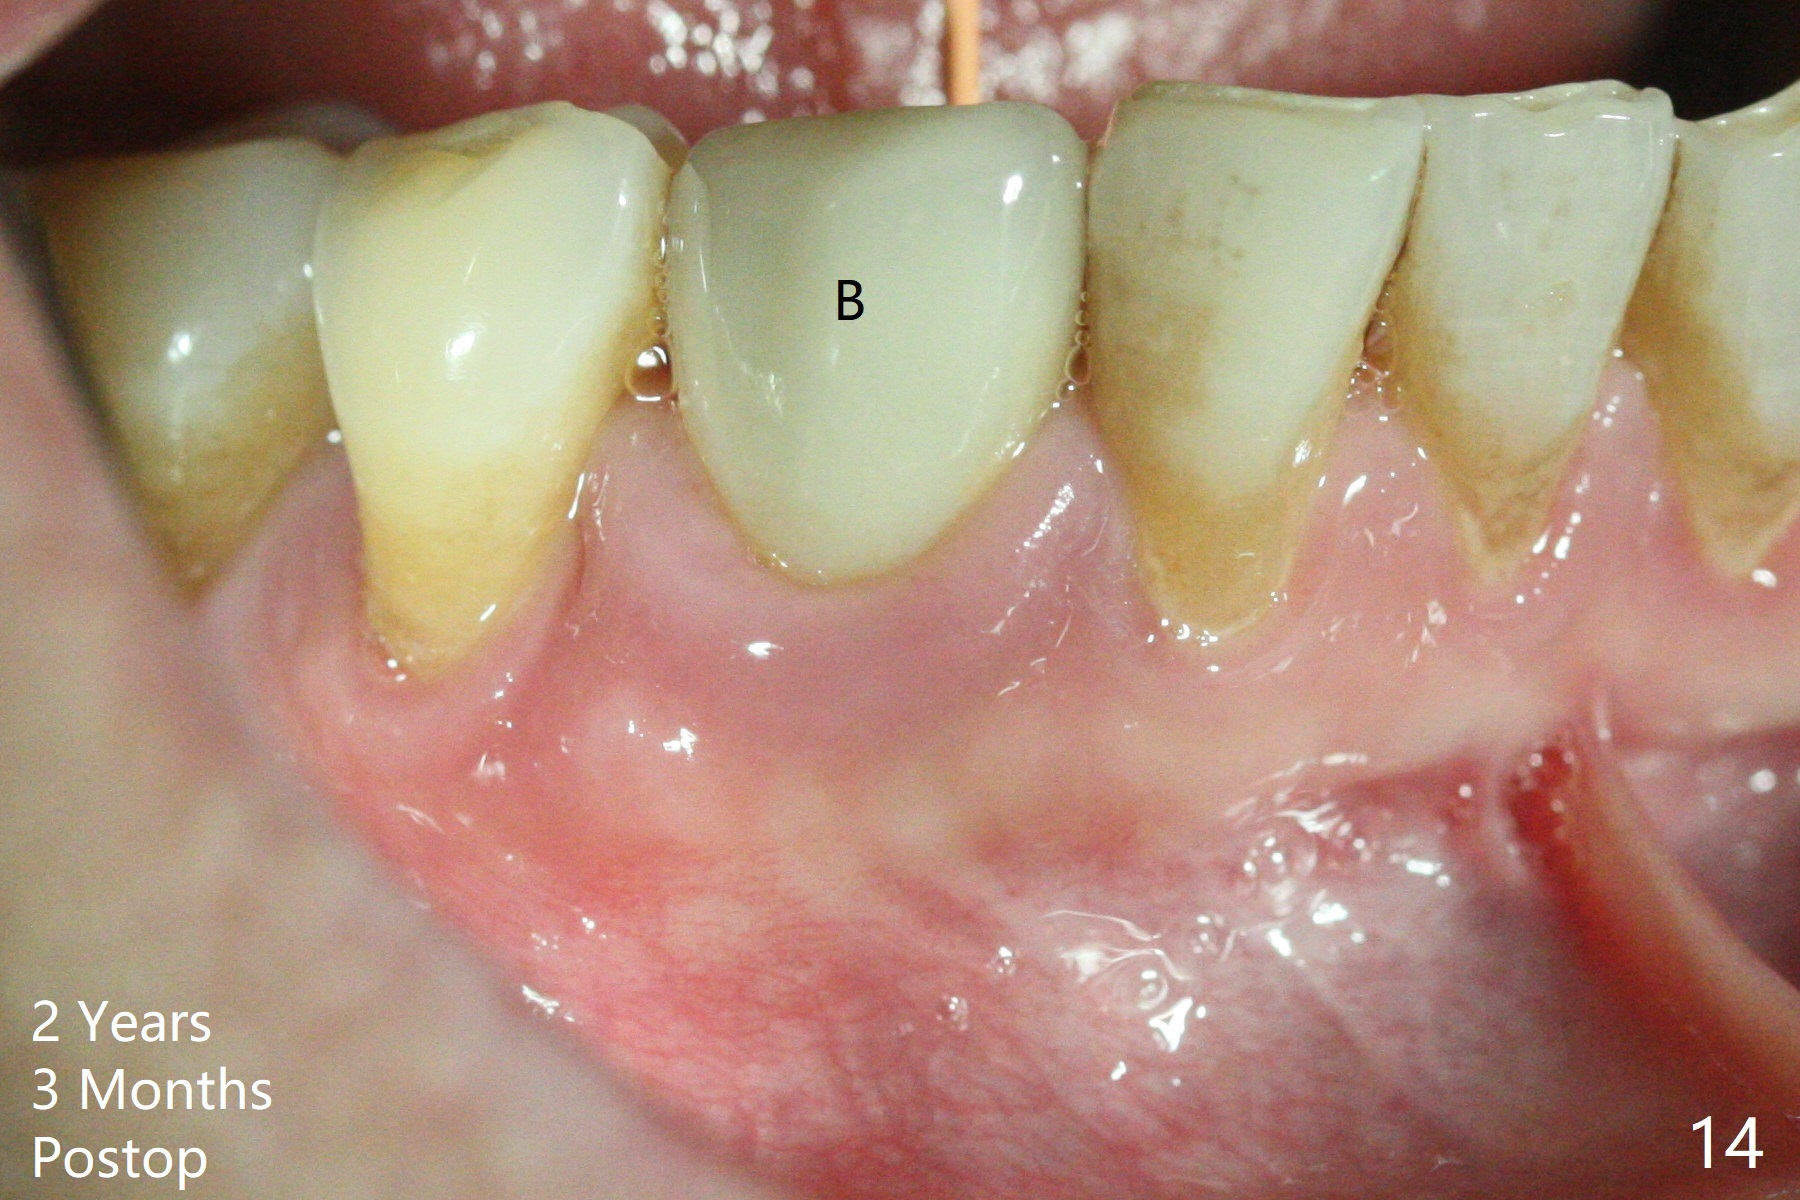

The patient reports that the fistula disappears after initial RCT at #27, but it seems to re-appear 1 month post canal debridement (Fig.5 >). After repeated debridement with #40 hand file at 23 mm, apply Endo Sequence BioCeramic Sealer and insert GT 40/.08 master cone with black carrier (Fig.6). One hour later, the patient returns with re-appearance of the fistula (Fig.7). Following local anesthesia, poking the fistula leads to sealer escape (Fig.8). After debridement of the fistula until the bone, PA is retaken (Fig.9). A crown was made in China; mesial radiolucency starts (Fig.10). The tooth remains asymptomatic 1 year 5 months postop (Fig.11). There is a lingual fistula with enlarged mesial radiolucency 2 years 3 months postop (Fig.12-14).